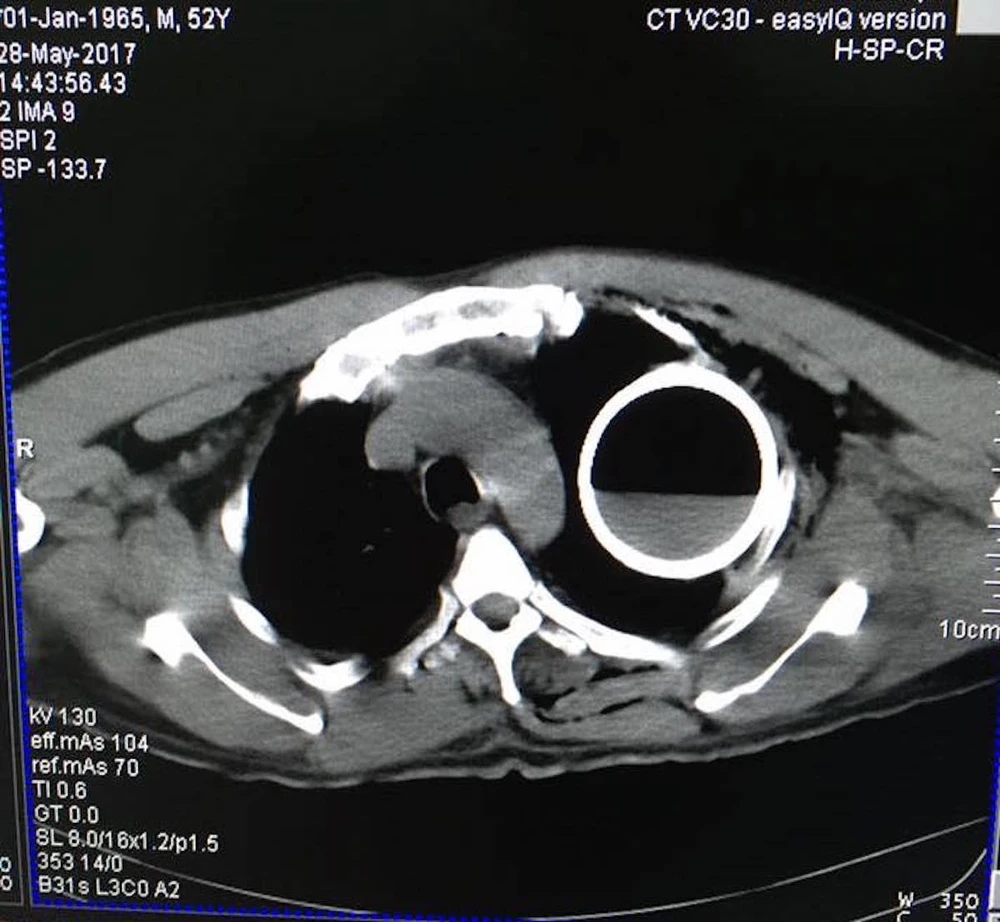

Hình ảnh chai nước qua màn hình chụp X-quang và CT. Ảnh: AB

Sau khi tiếp nhận bệnh nhân, BV đã tiến hành chụp X-quang và CT, các bác sĩ ngỡ ngàng khi thấy một vỏ chai thủy tinh còn nguyên vẹn trong lồng ngực bệnh nhân B.